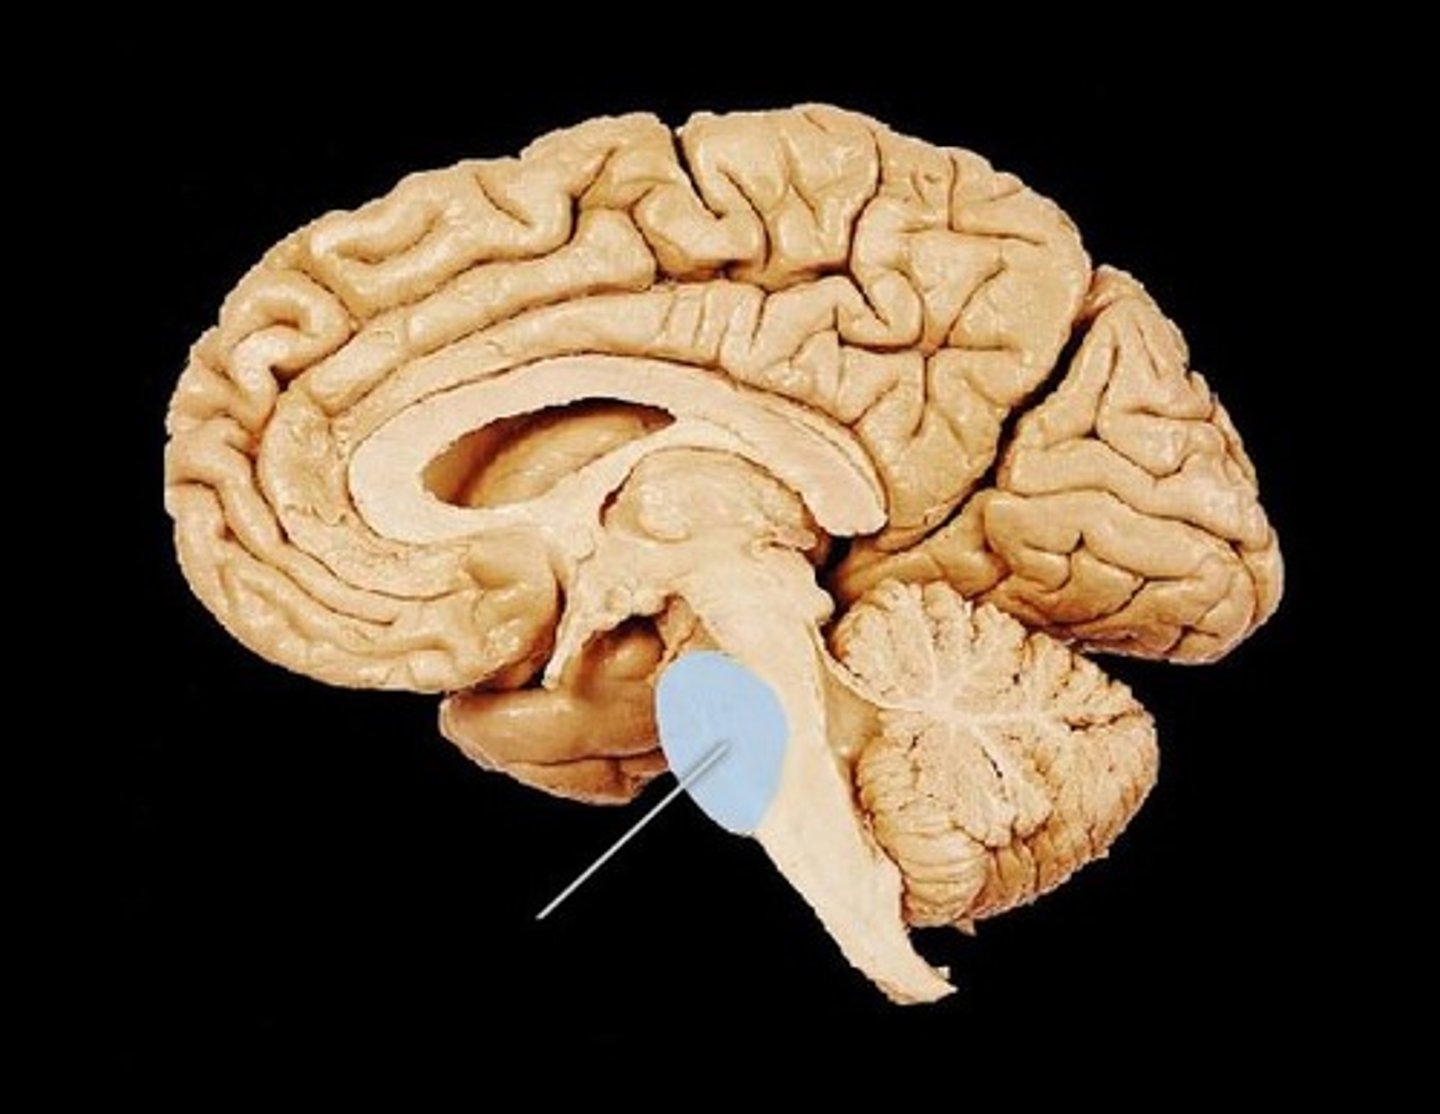

Cerebellum

"little brain" attach to the top of the brain stem. Components include vermis, arbor vitale, cortex, peduncles

Brain Stem

Continuation of spinal cord. Contains medulla oblongata, pons and midbrain

Pons

bulging brain stem region between midbrain and medulla.

Medulla Oblongata

most inferior part of brain stem, eventually becomes spinal cord. Autonomic reflex center.